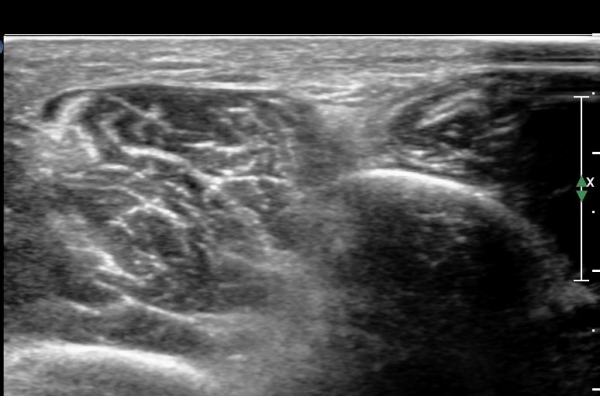

¾ÕÂÊ ¸»´Ü °æ°ñºñ°ñ°üÀý ¾à 5cm ±ÙÀ§ºÎ Ⱦ´Ü몀°Ë»ç ½Ã õºñ°ñ½Å°æ Àü¸é¿¡ Àú¿¡ÄÚ ³¶Á¾¿¡ ÀÇÇÑ ½Å°æ ¾Ð¹ÚÀÌ °üÂûµÈ´Ù(ÀÌ °üÂûµÈ´Ù(»çÁø 6, 7).